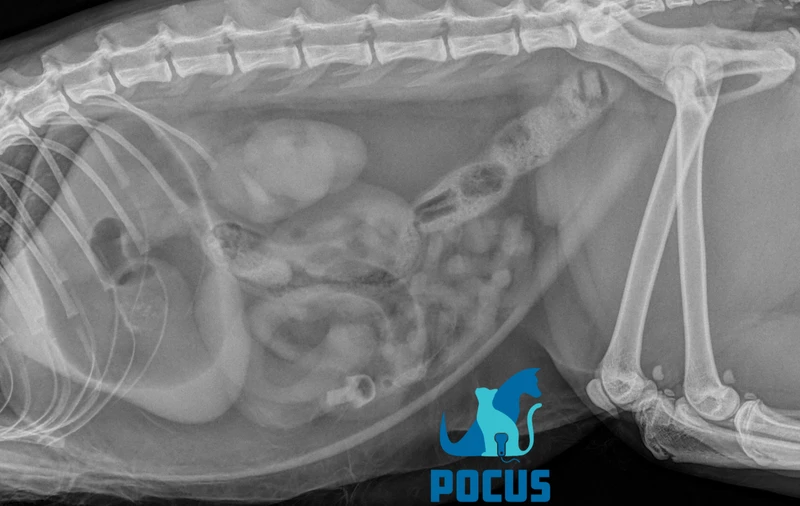

הדמיית מערכת העיכול בכלבים וחתולים - השילוב המושלם של רנטגן ואולטרסאונד